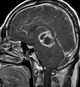

Central neurocytoma (CNC) is an extremely rare, ordinarily benign intraventricular brain tumour that typically forms from the neuronal cells of the septum pellucidum. The majority of central neurocytomas grow inwards into the ventricular system forming interventricular neurocytomas. [Source: Wikipedia ]